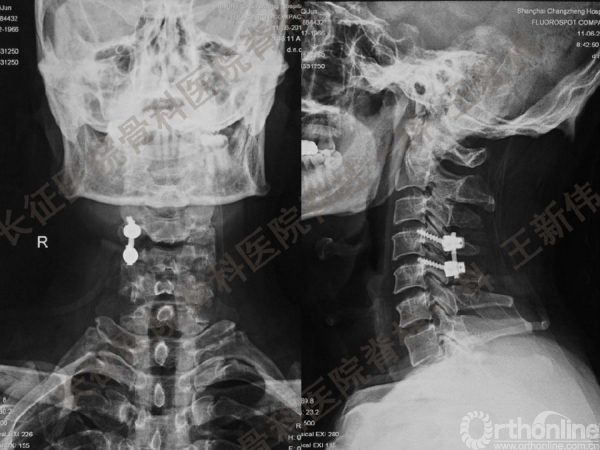

王新伟:颈椎后路通道下手术病例报告及文献回顾

颈椎后路通道下手术有哪些?颈椎后路通道下手术能做哪些事?颈椎后路通道下手术有哪些优势?长征医院骨科医院脊柱一科王新伟副教授通过临床病例报告及文献回顾,给出了他的答案——